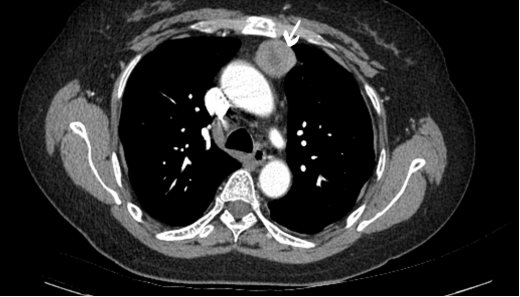

日前,我院外科团队成功为1位纵膈肿瘤患者施行了胸腔镜下纵隔肿瘤切除术,手术的成功标志着我院胸外科技术水平上了一个新台阶。 56岁的黄女士体检发现左上纵隔占位,肿瘤较大,且紧邻心脏大血管,恰似一颗“隐形炸弹”,入院后进一步检查提示,黄女士面临多重基础疾病威胁:慢性肾脏病Ⅲ期、贫血、双侧胸腔积液。 纵隔肿瘤的传统开胸手术不仅创伤大,还极有可能引发加重肾功能不全、肺部感染、呼吸衰竭、脓胸等多项并发症,而腔镜微创手术能在很大程度上减轻手术风险和并发症。 术前我院外科团队联合多学科对患者进行综合评估,并制定了针对性腔镜下治疗方案,排除手术禁忌,如肾病科团队就患者肾功能不全定制肾功能防护方案:避免肾毒性麻醉药物,术后皮下注射促红素纠正贫血,实现患者术后肌酐维稳等。 手术切口3cm主操作孔+1.2cm观察孔,术中通过仔细分离组织间隙,完整切除约3.0cm*3.0cm*2.5cm大小肿块,全程未损伤血管神经,控制出血量<50ml(为贫血患者守住了生命线),手术时间仅1小时,充分保护了患者肾功能。 术后医护人员共同密切监测患者生命体征、胸腔引流量等,并采用中西医结合治疗,促进患者术后康复,第3天即拔除胸腔闭式引流管,术后6日即康复出院! 我院外科团队本次自主完成胸腔镜下纵隔肿瘤切除术,不仅体现了外科团队技术水平的进一步提升,更减轻了患者外出就医负担。 宁国市中医院外科团队温馨提示:纵隔肿瘤因为累及部位不同,会引起不同的不适,如出现呼吸困难、发热、咳嗽、吞咽困难、声音嘶哑、声带麻痹等症状,请立即到医院就诊。 咨询电话:0563-4011813 上图为纵膈肿瘤位置标识 |